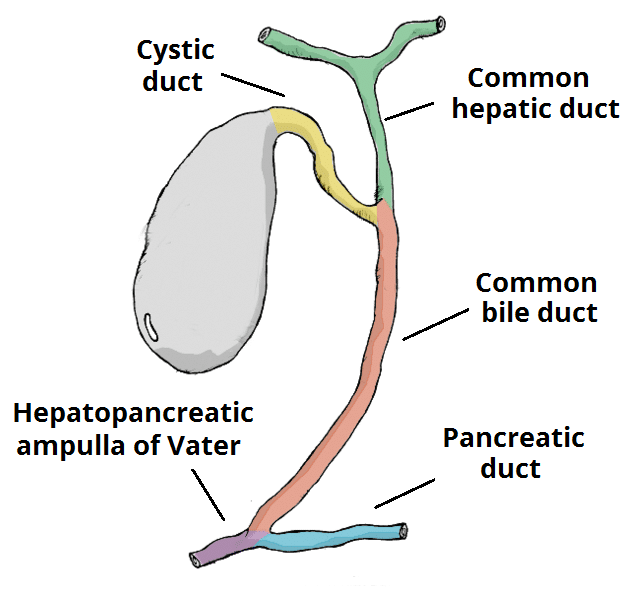

Pathophysiology

Each cause described above will trigger a premature and exaggerated activation of the digestive enzymes within the pancreas. The resulting pancreatic inflammatory response causes an increase in vascular permeability and subsequent fluid shifts (often termed “third spacing”).

Enzymes are released from the pancreas into the systemic circulation, causing autodigestion of fats (resulting in a ‘fat necrosis’) and blood vessels (sometimes leading to haemorrhage in the retroperitoneal space). Fat necrosis can cause the release of free fatty acids, reacting with serum calcium to form chalky deposits in fatty tissue, resulting in hypocalcaemia.

The majority of acute pancreatitis cases occur secondary to gallstone disease or excess alcohol consumption. However, causes are wide ranging and a popular mnemonic is ‘GET SMASHED’:

- Gallstones

- Endoscopic retrograde cholangio-pancreatography (ERCP)